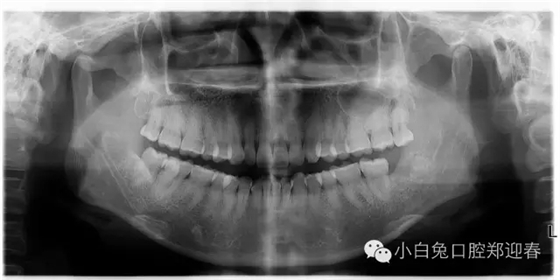

術(shù)前片子

一例智齒斷根進行二次拔除的感悟